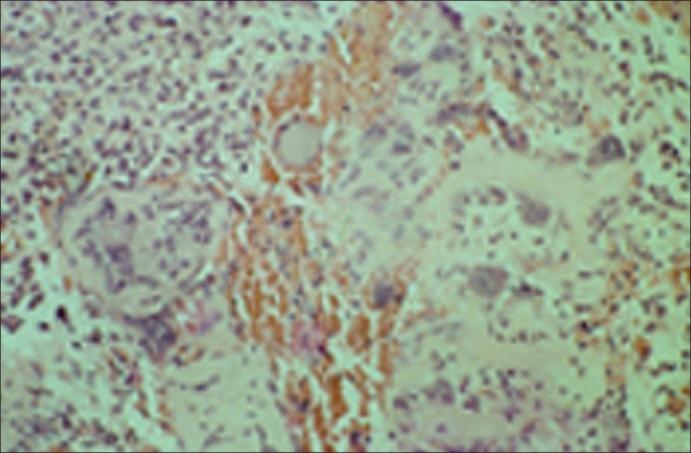

A pulse granuloma is nothing but a reaction of the foreign body to any vegetable which is characterized by a collection of the hyaline; a hyaline is a transparent substance that is formed from the pathological degeneration of the tissue. These granulomatous rings may be oral or extra-oral. It is important to recognize such a type of granuloma because it may resemble serious pathological processes or may clinically stimulate neoplasia. It might also be confused morphologically with hyaline vasculopathy. The following manuscript presents a rare case of oral pulse granuloma. As going by the literature-search, the following being the only case to have been occurred in a pediatric patient. The authors therefore aim to bring awareness amongst the pediatric dentists about its etiology, occurrence, clinical features and thereby management of the same.

脉管肉芽肿只不过是异物对任何蔬菜的一种反应,其特征是透明质的聚集;透明质是一种由组织病理变性形成的透明物质。这些肉芽肿性环可能发生在口腔内或口腔外。认识到这种类型的肉芽肿很重要,因为它可能类似于严重的病理过程,或者在临床上可能刺激肿瘤形成。它在形态上也可能与透明血管病相混淆。以下手稿介绍了一例罕见的口腔脉管肉芽肿病例。通过文献检索发现,这是唯一发生在儿科患者身上的病例。因此,作者旨在提高儿科牙医对其病因、发生情况、临床特征以及相应治疗方法的认识。